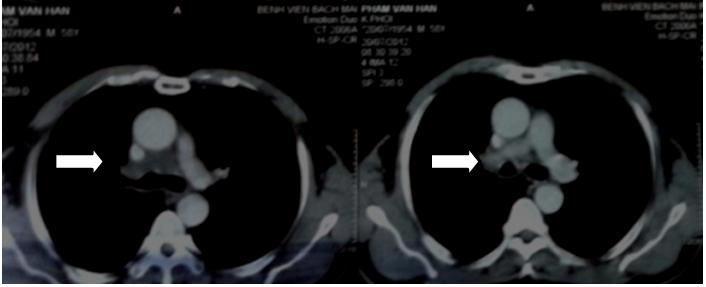

Hình 2: Chụp cắt lớp sau 6 tuần điều trị Navelbine: u tan một phần lớn

Kết quả: Cho thấy bệnh nhân sau 6 tuần điều trị đáp ứng tốt, u tan gần hoàn toàn, không phải thở oxy, đi lại sinh hoạt được. Hiện tại bệnh nhân ổn định, sau phác đò hóa chất Navalbine bệnh nhân được chuyển qua phác đồ hóa chất khác để có được đáp ứng triệt để hơn.